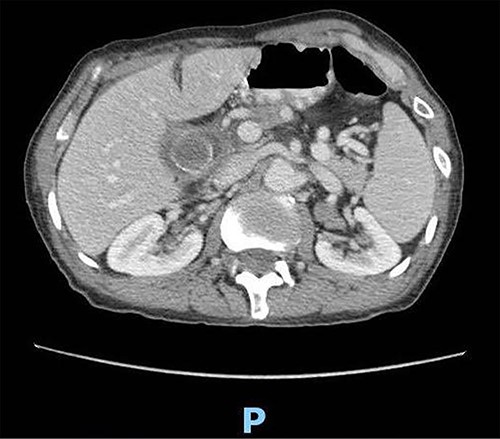

A 89-year-old male patient was admitted to the emergency department complaining of generalized abdominal pain for 4 days. The pain was associated with repeated vomiting and obstipation. He also reported a history of chronic constipation. However, he denied any history of melena, hematochezia, weight loss, night sweats or fever. His past medical history revealed a history of prostatic cancer and pulmonary fibrosis caused by tuberculosis. The patient was diagnosed with symptomatic gallstones two years prior to his presentation, after undergoing an enhanced CT scan of the abdomen (Fig. 1) for abdominal pain. Although he was offered cholecystectomy, he refused the surgery due to his high-risk medical condition.

Enhanced CT scan of the abdomen confirming the presence of a 2.5-cm gallstone.